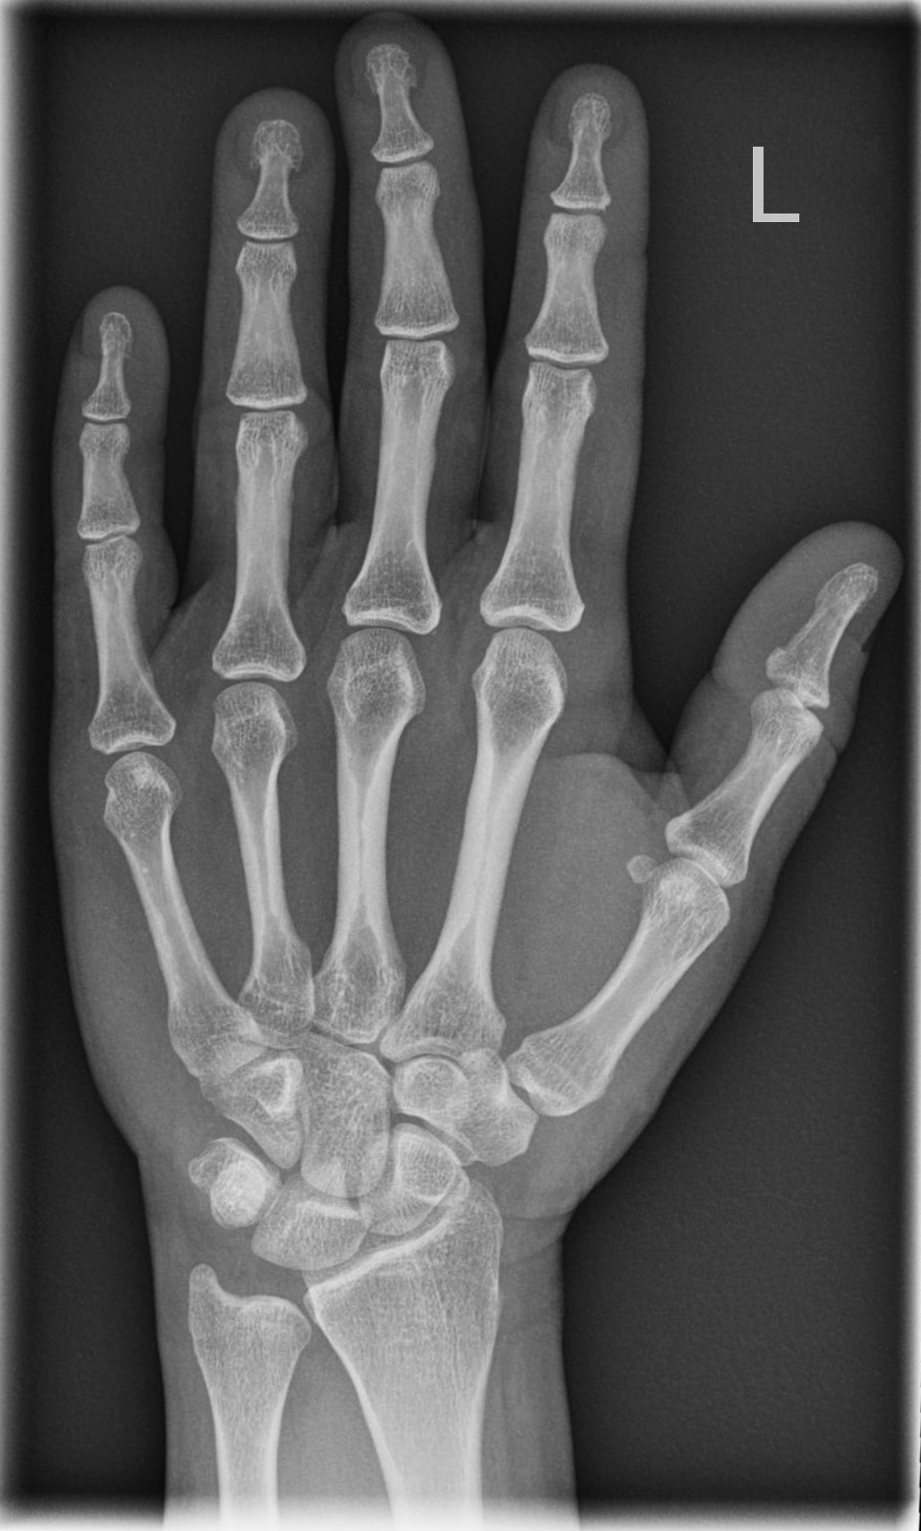

Hand d.v. (dorso-volar)

Indikation

Frakturen, entzündliche (Arthrose) und degenerative Veränderungen (Arthritis), chronische Polyarthritis (Rheuma)

Patient sitzt seitlich zum Tisch, Beine befinden sich neben Tisch abgewinkelter Unterarm und die Handfläche liegen auf.

senkrecht auf Objektmitte

proximal einschließlich Proc. styloideus radii und ulnae

Übersichtsdarstellung des Skeletts bei Frakturen, Arthrosis und Deformierung der Gelenke, sowie chronischer Polyarthritis (Rheuma).

Fragestellungsabhängige Einblendung mögl. z. B. Mittelhand

Qualitätskriterien

vollständige Darstellung der ganzen Hand inklusive Handgelenk, Buchstabe